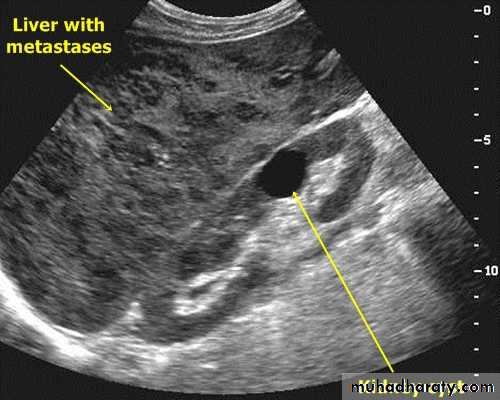

When multiple masses are seen, metastatic disease is the likely diagnosis. Other differential diagnosis include multiple abscesses and multiple hemangiomas.

At US, they may show increased echogenicity or, more usually, decreased echogenicity compared with the surrounding parenchyma. At times, they show a complex echo pattern and when they undergo central necrosis they may even resemble cysts.

A metastases may have an echogenic center giving an appearance of "target lesion".